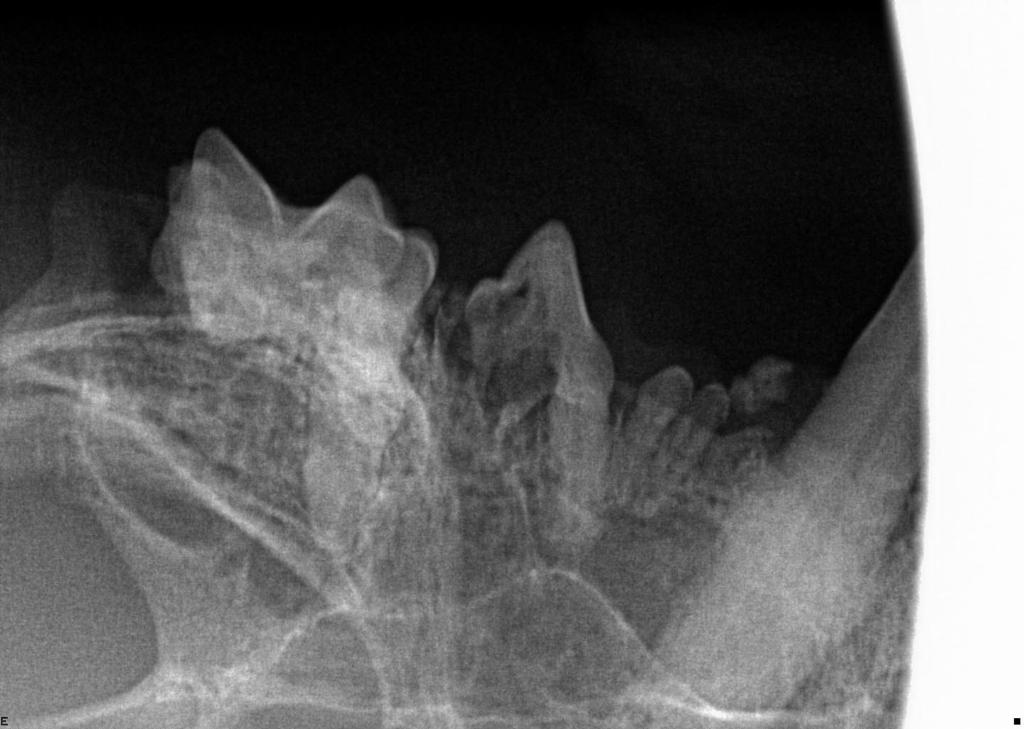

Dental X-Rays are especially important in feline dentistry. This is because cats very commonly get a disease called tooth resorption, where cells called odontoclasts destroy and dissolve the tooth, later replacing it with bone. This is a painful and irreversible disease and the only treatment is extraction of the affected teeth. Because the disease starts with the tooth root below the gumline and only starts affecting the visible crown of the tooth much later in the disease process, we cannot know which teeth are affected without taking radiographs.

Below shows an image of a normal tooth on dental X-Ray compared to a tooth that is undergoing tooth resorption in the three images below the main one.

Dental X-Rays can also be used in a number of other situations, including to assess for pulp necrosis, periodontal disease, jaw fractures and retained root fragments.